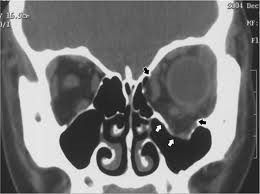

??? 眼眶疾病:眼眶骨折整復術、眶內腫瘤的摘除、甲狀腺相關性眼病和炎性假瘤的綜合治療、淚腺脫垂的修復。